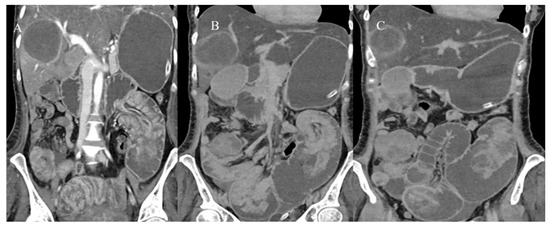

- Marsicovetere, P.; Ivatury, S.J.; White, B.; Holubar, S.D. Intestinal intussusception: Etiology, diagnosis, and treatment. Clin. Colon. Rectal Surg. 2017, 30, 30–39. [Google Scholar] [CrossRef] [PubMed]

- Kim, Y.H.; Blake, M.A.; Harisinghani, M.G.; Archer-Arroyo, K.; Hahn, P.F.; Pitman, M.B.; Mueller, P.R. Adult intestinal intussusception: CT appearances and identification of a causative lead point. Radiographics 2006, 26, 733–744. [Google Scholar] [CrossRef]

- Choi, S.H.; Han, J.K.; Kim, S.H.; Lee, J.M.; Lee, K.H. Intussusception in adults: From stomach to rectum. AJR Am. J. Roentgenol. 2004, 183, 691–698. [Google Scholar] [CrossRef]

- Panzera, F.; Di Venere, B.; Rizzi, M.; Biscaglia, A.; Praticò, C.A.; Nasti, G.; Mardighian, A.; Nunes, T.F.; Inchingolo, R. Bowel intussusception in adult: Prevalence, diagnostic tools and therapy. World J. Methodol. 2021, 11, 81. [Google Scholar] [CrossRef] [PubMed]

- Honjo, H.; Mike, M.; Kusanagi, H.; Kano, N. Adult intussusception: A retrospective review. World J. Surg. 2015, 39, 134–138. [Google Scholar] [CrossRef] [PubMed]

- Wang, N.; Cui, X.Y.; Liu, Y.; Long, J.; Xu, Y.H.; Guo, R.X.; Guo, K.J. Adult intussusception: A retrospective review of 41 cases. World J. Gastroenterol. World J. Gastroenterol. 2009, 15, 3303. [Google Scholar] [CrossRef]